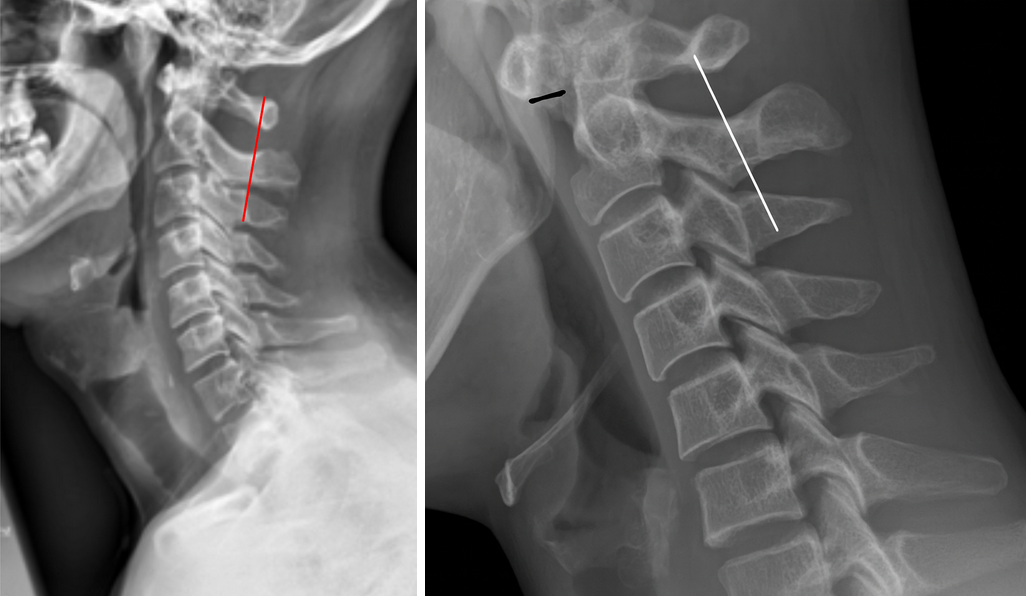

The Swischuk Line is a radiographic reference line used to distinguish pseudosubluxation (a normal physiologic finding in children) from true cervical spine injury, particularly at the C2–C3 level.

It is drawn along the posterior cortical margins of the spinolaminar junctions of C1 and C3, and the position of the C2 spinolaminar junction is evaluated in relation to this line.

• Identify the spinolaminar junctions (the point where the lamina meets the base of the spinous process) of C1, C2, and C3.

• Draw a straight line connecting the spinolaminar junction of C1 to the spinolaminar junction of C3 — this is the Swischuk Line.

• Locate the spinolaminar junction of C2 and determine its position relative to the Swischuk Line:

• If the C2 spinolaminar point lies within 1–2 mm of the Swischuk Line → Normal (pseudosubluxation).

• If the C2 spinolaminar point is more than 2 mm anterior to the line → Abnormal (suggests true subluxation or dislocation).